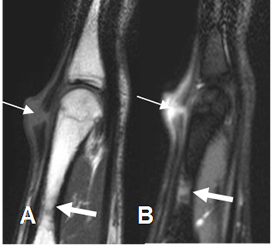

Fig 65. Lesión del mecanismo extensor.

A: RM sagital en T1 y B: RM sagital en STIR. Ruptura no retraída del tendón extensor, sobre el tercio distal del metacarpiano. Adicionalmente hay contusión osea. (Flecha gruesa).